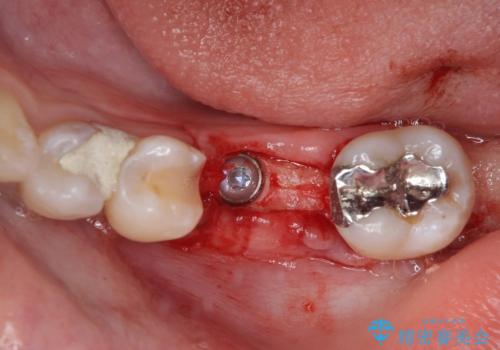

- ブリッジの歯のないところにインプラントを入れて、銀歯を白くやり替えたいと来院された患者様です。

歯の欠損している箇所にはインプラント治療をし、銀歯と仮詰めの部分はセラミックインレーにて補綴することとしました。

すべての治療の前に親知らずの抜歯も行っています。